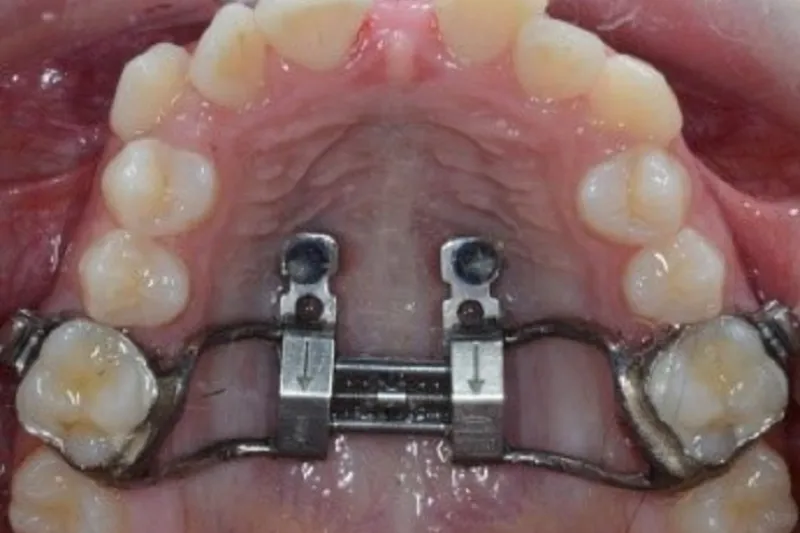

Imidlertid nødvendiggør ekstrem maksillær hypoplasi oftest ortodontisk-kirurgisk behandling involverende kirurgisk assisteret ganeekspansion med sprængning af den midtpalatinale sutur og/eller sektioneret Le Fort I-osteotomi.

Maksillær hypoplasi kendetegnes ved manglende vækstudvikling i maksillen, transversale okklusionsafvigelser og tendens til udvikling af klasse III-malokklusion. Vækstforstyrrelser i maksillen og transversale okklusionsafvigelser kan i mange tilfælde kompenseres og korrigeres ved vækstadapterende behandling, hvis rettidig interceptiv behandling iværksættes. Imidlertid nødvendiggør ekstrem maksillær hypoplasi ofte ortodontisk-kirurgisk behandling involverende kirurgisk assisteret ganeekspansion med sprængning af den midtpalatinale sutur og/eller sektioneret Le Fort I-osteotomi. Tidlig diagnostik og iværksættelse af relevant behandling er derfor vigtigt ved maksillær hypoplasi og klasse III-malokklusion for at opnå et tilfredsstillende behandlingsresultat med færrest mulige invasive procedurer og gener for patienten.